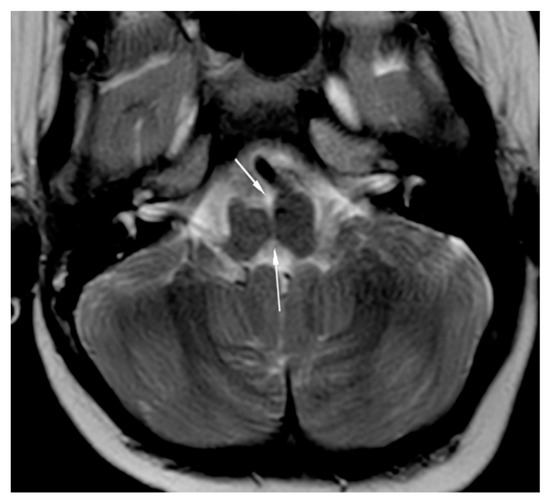

Brain magnetic resonance imaging (MRI) demonstrated hypoplasia of the brainstem (Figure 2), a left thalamus volume larger than the right (Figure 3), an enlarged fourth ventricle, an anterior and posterior midline bulbar and pontine cleft (split-pons sign) (Figure 4), a butterfly configuration of the medulla (Figure 5), an occipital and parietal plagiocephaly on the right side, and a slight benign enlargement of the subarachnoid spaces in the frontotemporal area. There were no signal changes within the medulla or pons in any of the brain MRI sequences.

Figure 5. MRI brain axial T2-weighted image showing butterfly medulla oblongata.